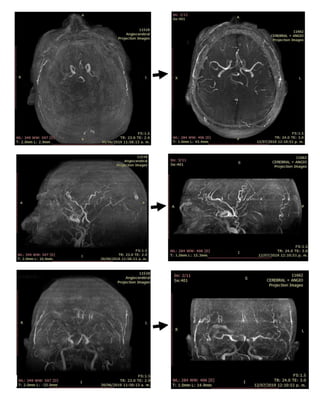

La tomografía cerebral no reveló alteraciones por lo que se realizó resonancia magnética

sospecha de síndrome de vasoconstricción cerebral reversible se decidió realizar

angioresonancia cerebral fase arterial y fue evidente una disminución en la luz como

“imagen en sacacorchos” de los bucles y trayecto de circuitos posterior y anterior; se

diagnosticó síndrome de vasoconstricción cerebral reversible y se inició metilprednisolona

1 g/día y nimodipina 60 mg cada 24 horas, la paciente presentó mejoría en nivel de

consciencia 48 horas después, en 2 semanas se realizó control de angioresonancia

evidenciando dilatación vascular lo cual confirmó el diagnóstico y teniendo como resultado

clínico la recuperación completa de la paciente.

Figura 6. Estudio control. Carótida izquierda

Figura 3. Primer estudio. Circuito anterior Figura 4. Estudio control. Circuito anterior

Figura 5. Primer estudio. Carótida izquierda

Figura 7. Primer estudio. Carótida derecha Figura 8. Estudio control. Carótida derecha.

Figura 9. Primer estudio. Circuito posterior

Figura 9. Estudio control. Circuito posterior

Discusión: La demostración de “imágenes como en sacacorchos” o estrechez segmentaria

y multifocal en la angiografía cerebral representó el pilar diagnóstico y enfoque terapéutico